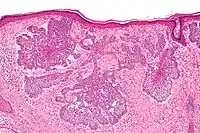

Micrograph of a basal-cell carcinoma, showing the characteristic histomorphologic features (peripheral palisading, myxoid stroma, artefactual clefting). H&E stain

Basal-cell carcinoma is named after the basal cells that populate the lowest layer of the epidermis due to the histological appearance of the cancer cells under the microscope.[16] Nevertheless, not all basal-cell carcinomas actually originate within the basal layer.[16] Basal-cell carcinomas are thought to develop from the folliculosebaceousapocrine germinative cells known as trichoblasts. Trichoblastic carcinoma is a term used to describe a rare and potentially aggressive malignancy that is also thought to arise from trichoblasts and may resemble a benign trichoblastoma (differential diagnosis can be challenging).[17][18][19] It has been suggested that lesions diagnosed as 'trichoblastic carcinoma' may actually themselves be basal-cell carcinoma.[20]

Nodular basal-cell carcinoma (also known as "classic basal-cell carcinoma") accounts for 50% of all BCC.[29] It most commonly occurs on the sun-exposed areas of the head and neck.[30]:748[31]:646 Histopathology shows aggregates of basaloid cells with well-defined borders, showing a peripheral palisading of cells and one or more typical clefts.[29] Such clefts are caused by shrinkage of mucin during tissue fixation and staining.[32] Central necrosis with eosinophilic, granular features may be also present, as well as mucin. The heavy aggregates of mucin determine a cystic structure. Calcification may be also present, especially in long-standing lesions.[29] Mitotic activity is usually not so evident, but a high mitotic rate may be present in more aggressive lesions.[29] Adenoidal BCC can be classified as a variant of NBCC, characterized by basaloid cells with a reticulated configuration extending into the dermis.[29]